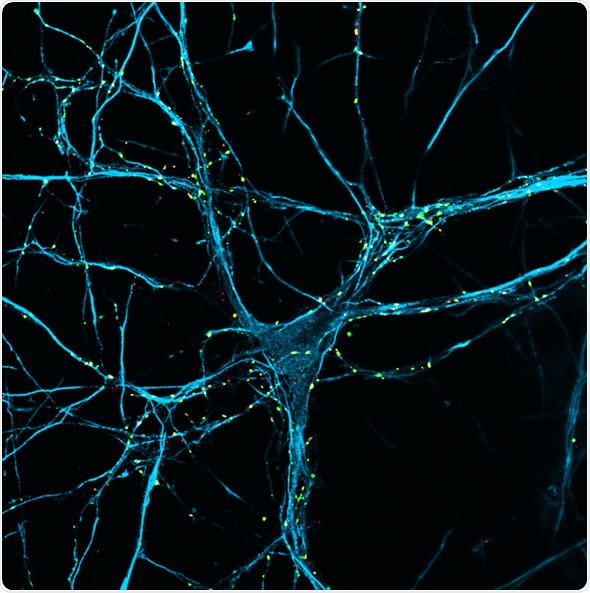

Image credit: Dr Galli / Parkinson’s UK